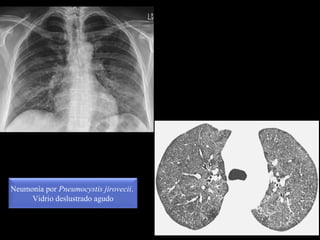

Vidrio deslustrado

Neumonía por Pneumocystis jirovecii.

Vidrio deslustrado agudo